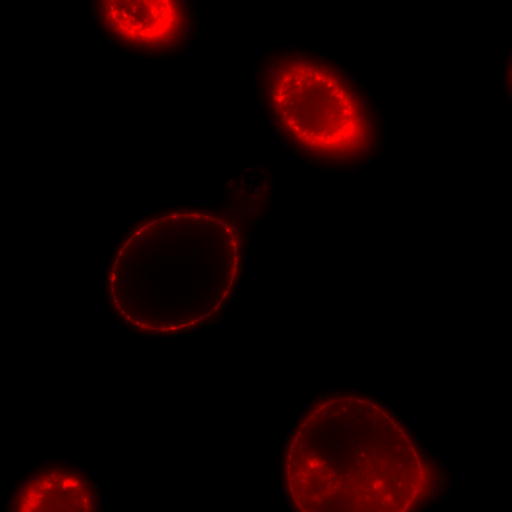

ナマズなどの魚卵には,ラムノース結合性レクチン(RBL)が含まれている.ナマズ卵由来RBL(SAL)は285アミノ酸から成り,95残基ずつの互いに相同性の高い3つのドメインから成る繰り返し配列を有するタンパク質で,バーキットリンパ腫細胞(RajiやDaudi)の糖脂質グロボトリアオシルセラミド(Gb3)に選択的に結合し,この細胞を短時間で縮小させる.しかし,細胞死は誘導しないユニークな性質を持っている.また,SALはこれらの細胞の細胞周期を停止させ,細胞増殖を阻害する働きもある.SALを利用して糖脂質糖鎖の情報伝達機構を明らかにできる可能性がある.